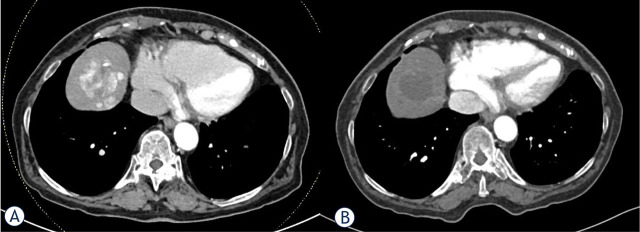

Abstract Image